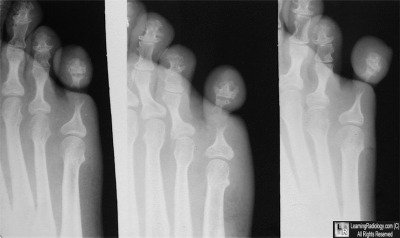

Case of the Week 505

What is the most likely diagnosis?

• 40 year-old from Africa with pain in little toe

Three views of right foot

3. Ainhum

Ainhum

General considerations

• Rare disorder in the US but relatively common amongst black Africans

• Autoamputation (dactylolysis) of a digit, usually the fifth toe

• Frequently bilateral (60%)

• Caused by a constricting fibrous band or groove

• Affects predominantly black males in tropical areas

• Has a familial association

• May be associated with running barefoot

• Rare before the age of 30 or after 50